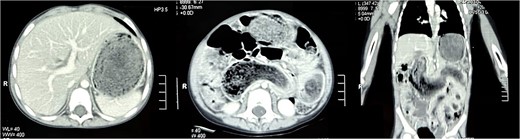

Laboratory investigations revealed iron deficiency anemia as the only significant finding. Abdominal ultrasound demonstrated multiple gas-filled bowel loops suggestive of incomplete obstruction. Subsequently, a contrast-enhanced computerized tomography (CT) scan of the abdomen revealed gastric and small bowel distension, along with a well-circumscribed homogeneous mass exhibiting a mottled gas appearance, suggestive of the presence of air and undigested food material (Fig. 1). The intraluminal mass displayed a characteristic hairball-like pattern, extending from the stomach to the distal jejunum, with small areas of hypodensity indicative of gastric and small bowel trichobezoar, consistent with Rapunzel syndrome. Additionally, a well-defined round lesion with a swirl pattern, suggestive of intussusception, was observed near the left iliac fossa.

Transverse section of the CT scan of the abdomen revealing non-contrast enhancing, well-circumscribed homogenous mass in the stomach (left). Coronal section of the CT scan of the abdomen revealing the mass extending from the stomach all the way into jejunum (right).